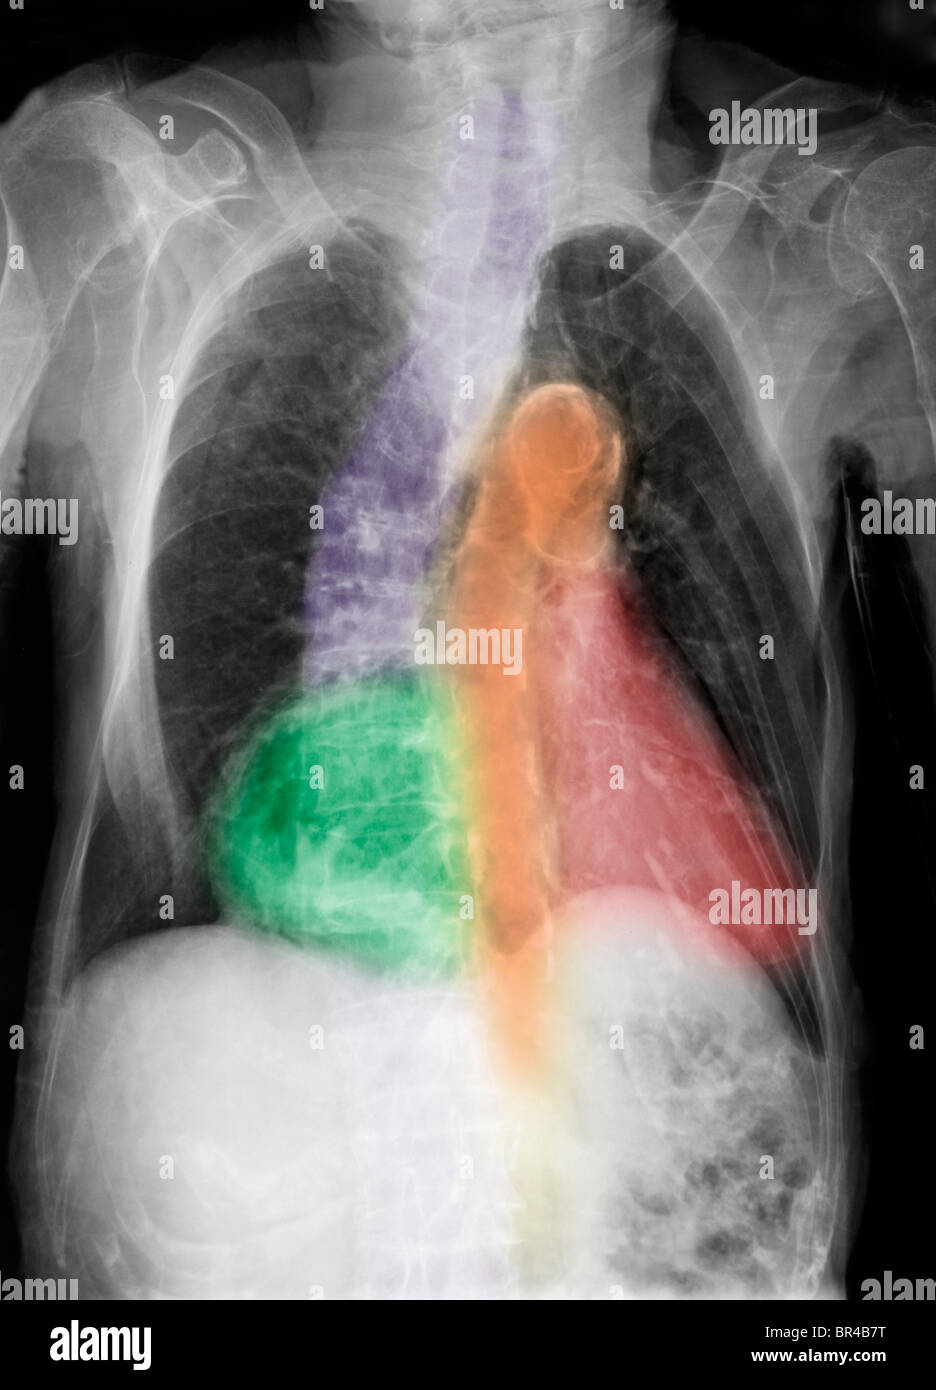

xray showing a hiatal hernia in an 82 year old person Stock Photo Alamy Chest X Ray Hiatal Hernia An upper gi barium series is the preferred examination in. tests that can diagnose a hiatal hernia include: It will classically appear as a mass with an air fluid level. — a hiatal hernia is often discovered during a test or procedure to determine the cause of heartburn or pain. — a hiatus hernia (also called hiatal. Chest X Ray Hiatal Hernia.